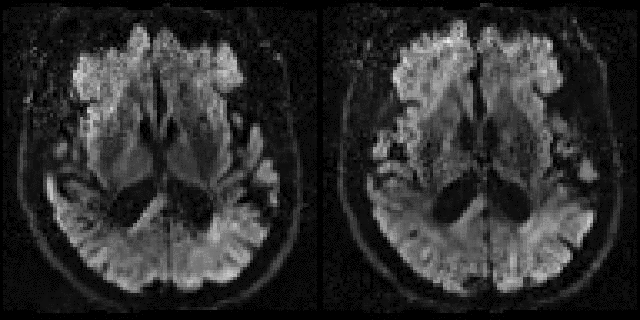

| Gaussian Process fit to multi-shell data. |

![]() |

| The figure shows data-points from a $b=1000$ shell (blue points) and a $b=3000$ shell (red points) from a voxel with a three-fibre crossing. For a given point, the distance from the centre shows the image intensity and the direction shows the diffusion gradient direction for the pertinent volume. The Gaussian Process fit is shown as a blue mesh for the $b=1000$ and a red for the $b=3000$ shell. It can be seen how well the Gaussian Process is able to model the rather complex signal in this voxel. |